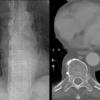

paraspinal lines

Date: 10/23/2010

Views: 3546

Views: 3261

Views: 3130

paraspinal interface

Date: 04/02/2014

Views: 3902